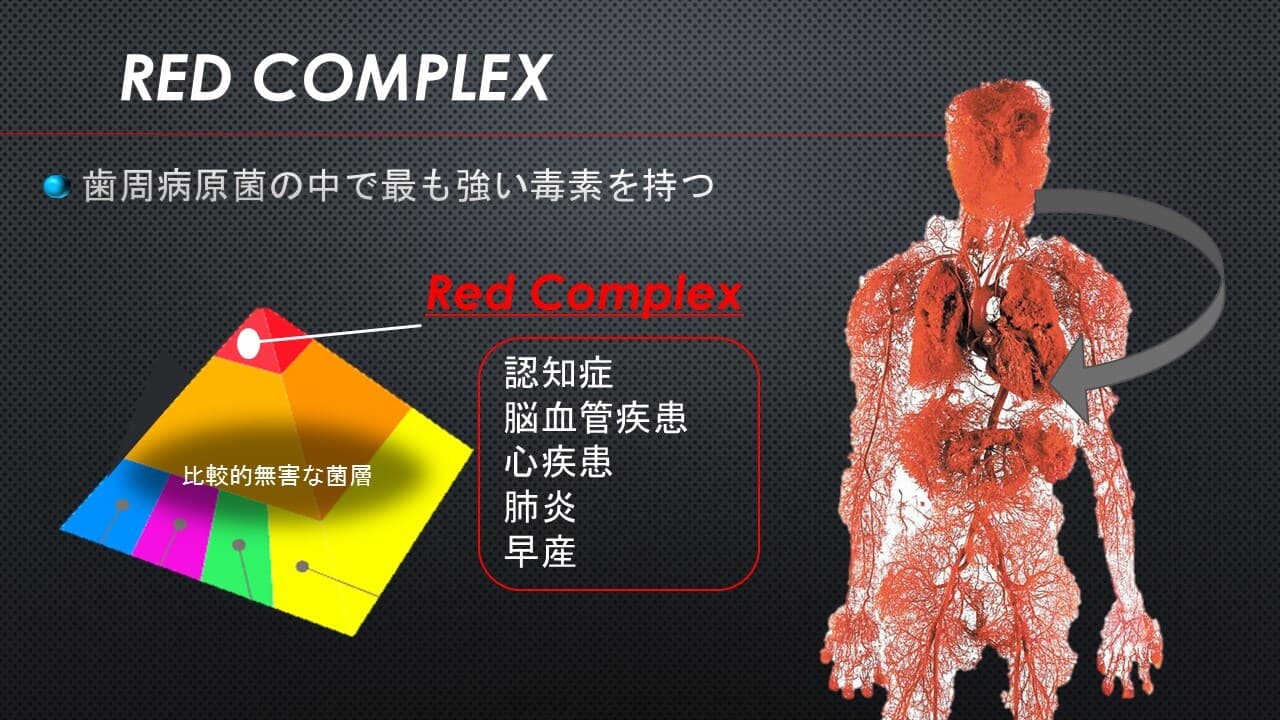

世界水準の光殺菌治療

こんにちは。南館歯科クリニックの歯科衛生士の山崎です。 早速ですが、当院で行っている歯周病専門治療の中にLAD(PDT)治療というものがあります。 聴いたことがない方が多いかと思いますが、それもそのは…